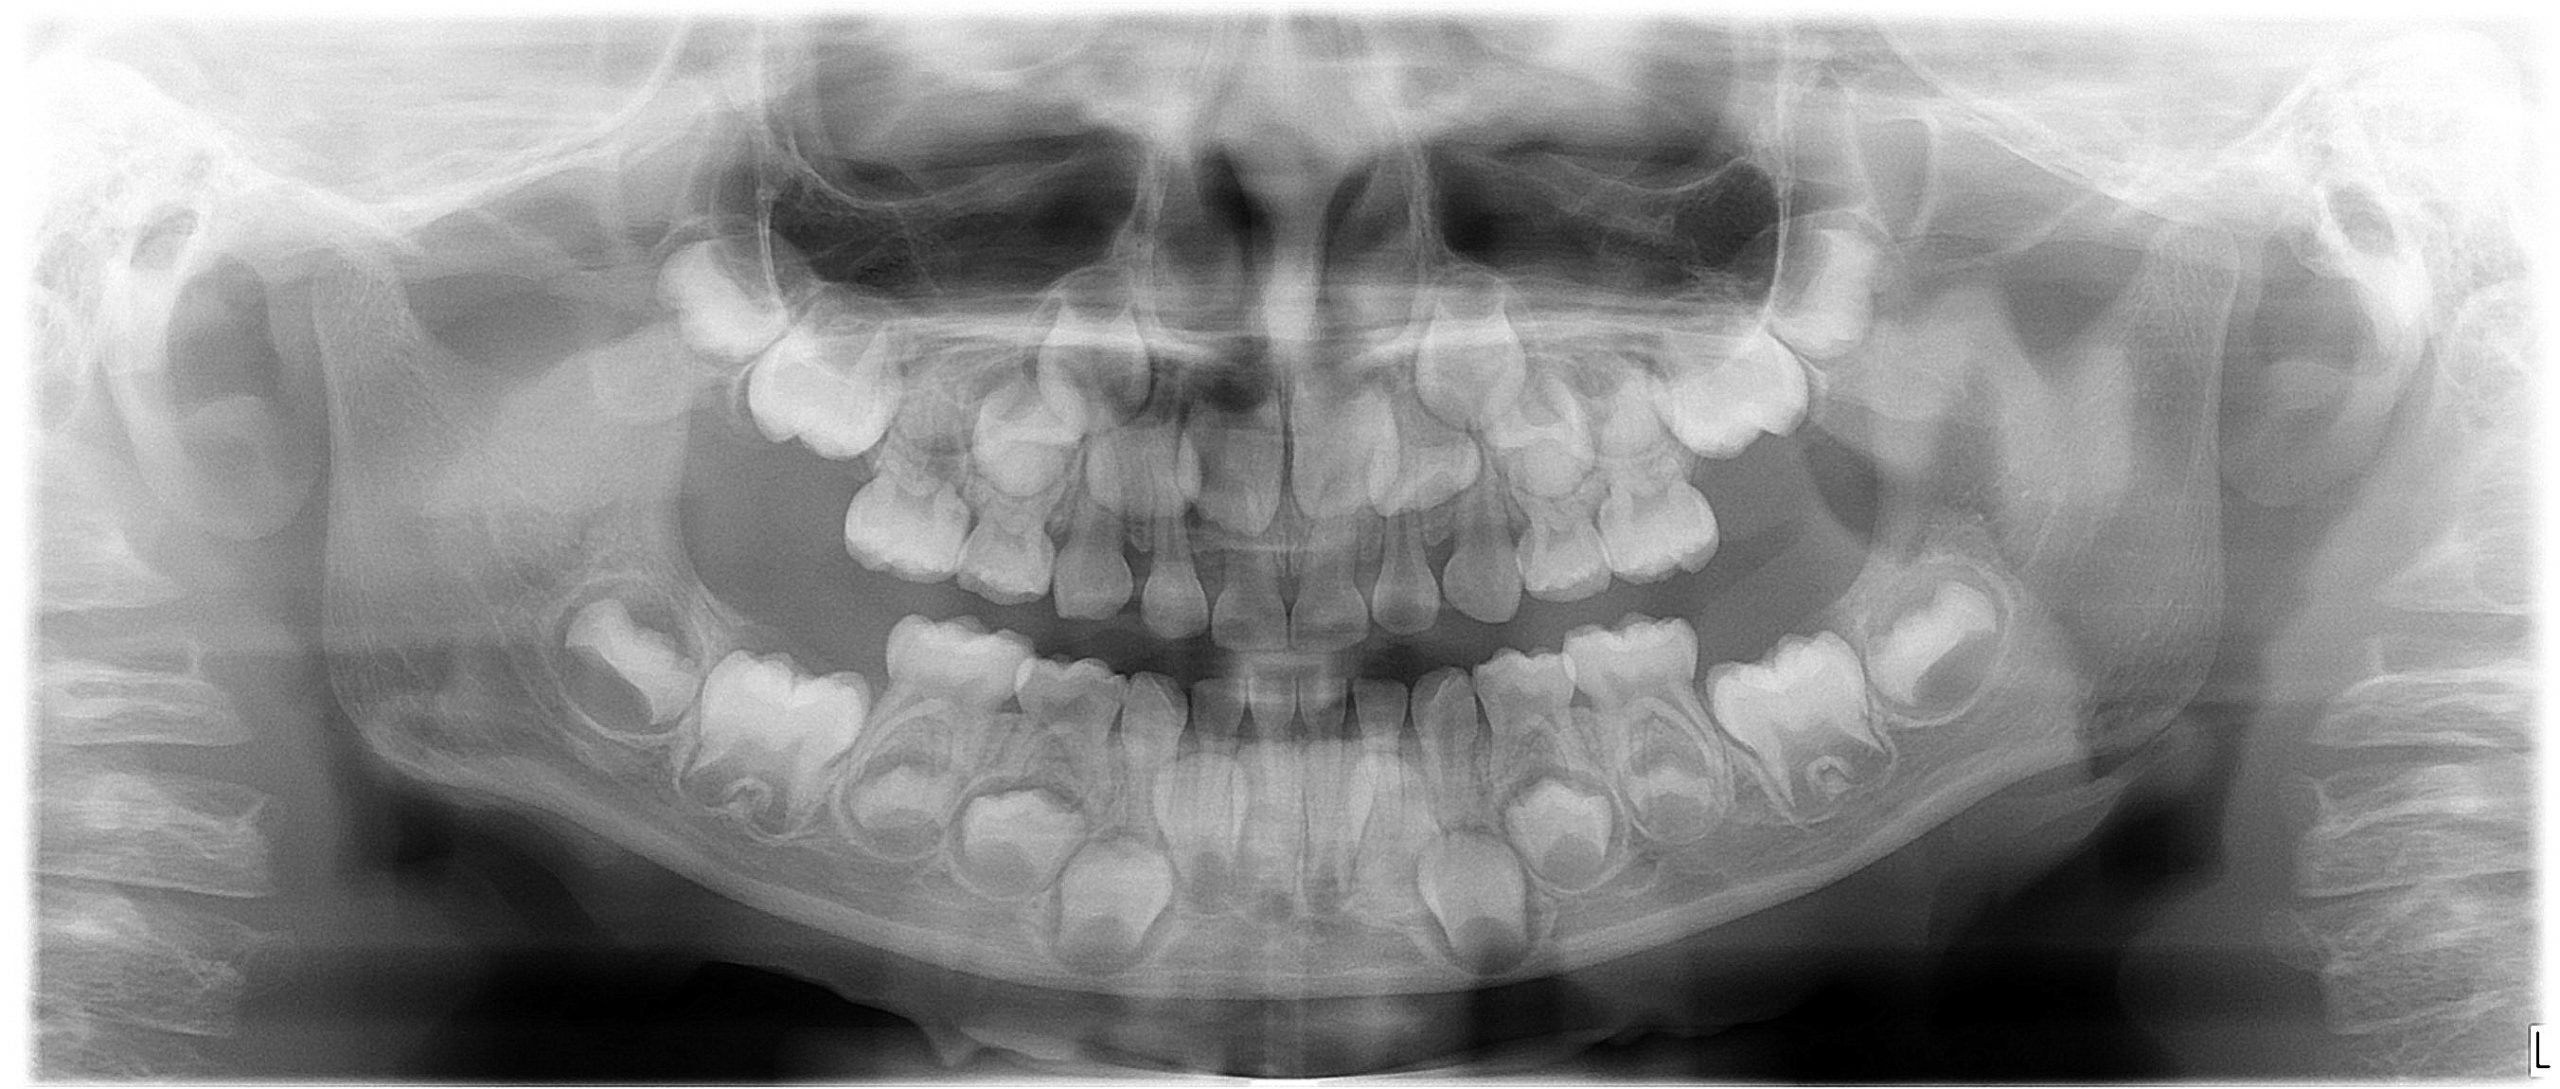

しっかりとレントゲン画像で、生えてくる永久歯に問題ないことが確認できていれば、歯の生え変わりがのんびりなのは心配いりません。

(お掃除や虫歯チェックで通っているだけではお子さんの場合はレントゲンを撮らない場合も多いのですが、必要な時にはレントゲン画像でのチェックが大切です)

【6歳のお子さんのレントゲン画像:乳歯の下にこれから生えてくる永久歯が控えています】